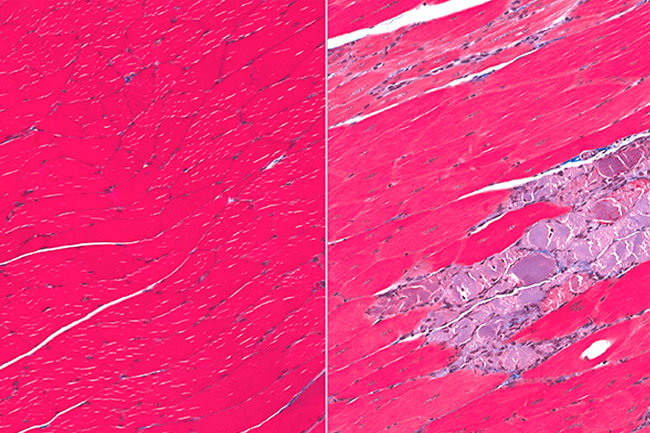

Поражение мышечных тканей

Поражение мышечных тканей 116 фото